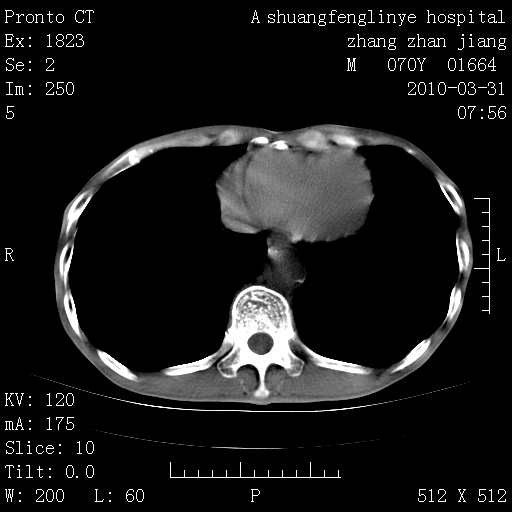

双上肺继发型tb并左上空洞形成,主动脉冠脉钙化。

支持:继发性肺结核伴空洞形成!建议纤支镜检查待出外周围型肺癌可能!

1)两肺上叶继发性肺结核并左肺上叶空洞形成。2)冠状动脉及主动脉钙化。